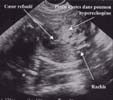

L'échographie met en évidence une masse intra-thoracique [7] :

Le doppler couleur ne retrouve pas de flux à l'intérieur de ces kystes. Il ne retrouve pas non plus de vascularisation aberrante provenant directement de l'aorte.

A ces signes directs peuvent s'associer :